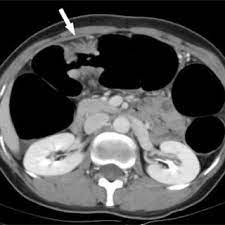

Can Cat Scan Find Colon Cancer / Molecular Imaging Using Positron Emission Tomography In Colorectal Cancer Michael Lin Discovery Medicine / Colonoscopy is best known for its use as a screening tool for the early detection of colorectal cancer.. Ct scans can produce false negatives and false positives. In addition to intraluminal structures like polyps, a ct scan of the colon can also detect extraluminal abnormalities. Dad also had a biopsy done a fortnight ago. Identifying these lesions on ct scan performed for nonspecific symptoms can help identify interval crc and improve patient outcome. Binderow continues, ct is very good for solid organ disease — liver, spleen, kidneys.

Ct Scan Uses Side Effects Procedure Results from www.verywellhealth.com Ct scan of the colon has the advantage of being less invasive than colonoscopy. Ct scans can produce false negatives and false positives. Estimates that any one person's risk of cancer from a ct scan is much lower than their risk of getting cancer naturally. Colorectal cancer is the 3rd most common type of cancer and the 3rd leading cause of cancer death in the united states. It can show metastatic colon cancer that has spread to the liver. If your ct was clear you can at the very least rule out a later stage of colon cancer. Ct colonography is a computed tomography (ct) examination to look at the large bowel (colon). Just a couple corrections to the other answers.

Ct scans overstaged and understaged ct in 23.7% and 48.3% and cn in 28.7% and 53.0% of cases. The endoscopy has an additional benefit of allowing small polyps to be biopsied or removed. The scan is painless and takes about 10 to 30 minutes. None of my ct scans report about the colon tumour. I performed an scope examination of her esophagus and confronted a huge cancer occupying the lower portion of her esophagus. Ct colonography (also known as virtual colonoscopy) can be used to screen for both large colorectal polyps and colorectal tumors.ct colonography uses the same dose of radiation that is used in standard ct of the abdomen and pelvis. It is a method of diagnosing bowel cancer when it is still at an early stage. To try to detect recurrences as early as possible, people who have finished colorectal cancer treatment regularly return to their doctors for imaging tests (like ct or mri scans) and a blood test to detect cea, a substance that can indicate if cancer is growing. Early colorectal cancer can be subtle on ct scans showing only mild wall thickening, small polyps, or subtle lymph nodes in atypical draining location. Pet scans are not routinely done in people diagnosed with colorectal cancer. Binderow continues, ct is very good for solid organ disease — liver, spleen, kidneys. A ct scan can be wrong: Posted 2 years ago, 5 users are following.

Unsuspected Colorectal Carcinoma On Routine Abdominopelvic Computed Tomography Smj from www.smj.org.sg Ct scans and mris are used more often. I expected a benign explanation for her swallowing issue. A female patient came to see me with some difficulty swallowing, a very routine issue for a gastroenterologist. Binderow continues, ct is very good for solid organ disease — liver, spleen, kidneys. Ct scans can be misread or misinterpreted. Colorectal cancer is the 3rd most common type of cancer and the 3rd leading cause of cancer death in the united states. Binderow, md, facs, fascrs, with northside hospital in georgia. It is a method of diagnosing bowel cancer when it is still at an early stage.

Dad also had a biopsy done a fortnight ago. A female patient came to see me with some difficulty swallowing, a very routine issue for a gastroenterologist. None of my ct scans report about the colon tumour. Pet scans are not routinely done in people diagnosed with colorectal cancer. I wonder why it doesn't show up. A ct scan can be wrong: Colorectal cancer is the 3rd most common type of cancer and the 3rd leading cause of cancer death in the united states. Ct scans overstaged and understaged ct in 23.7% and 48.3% and cn in 28.7% and 53.0% of cases. Unlike screening exams, which primarily find cancer in the colon, these staging exams help your doctor check the rest of your body for cancerous cells that may have metastasized, or spread, outside of the colon. Early colorectal cancer can be subtle on ct scans showing only mild wall thickening, small polyps, or subtle lymph nodes in atypical draining location. Imaging tests usually can't tell if a change has been caused by cancer. A ct is not the best test to diagnose colon cancer. Does/or did your colon, rectal tumour show in the ct scan, and did the radiologist report on it.